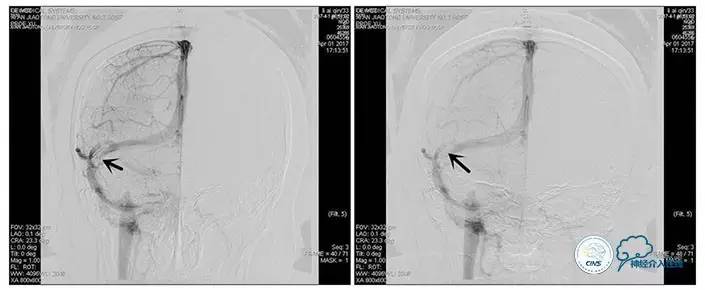

术中造影

5ml/s,总量8ml,压力100~150

手术方案

1、6mm×20mmAviator球囊(Cordis)分段对狭窄部位进行扩张。

2、植入7mm×40mmPrecise自膨支架。

术后造影

术毕远近端压力差为:0